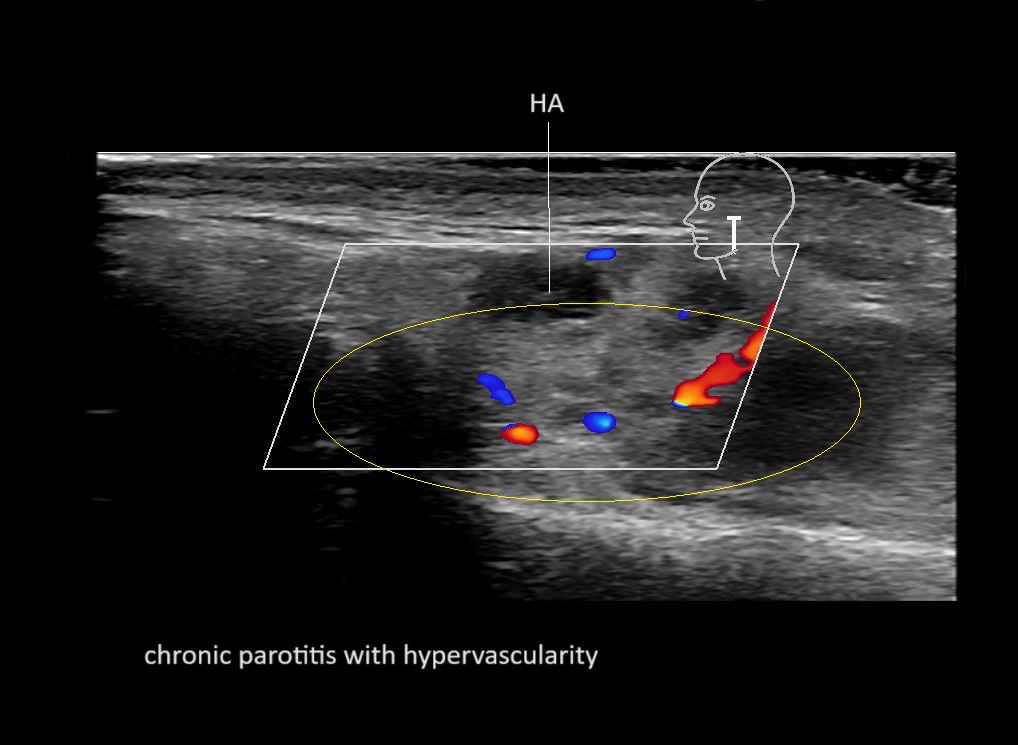

With ultrasound signs of inflammation can be visualized. Edema can be seen as a hyperechoic appearance of the subcutaneous fat, sometimes separated by hypoechoic fluid filled area’s, known as cobblestone appearance. Increased vascularization (hypervascularity) can be seen on colour Doppler. An abscess will appear as a fluid collection appearing as an irregular hypoechoic area with heterogeneous internal echoes and a thickened wall. Posterior acoustic enhancement can be present, and there is vascularity around but not within the mass. Under ultrasound guidance, abscesses can be managed by needle aspirations (18G) under antibiotic cover.